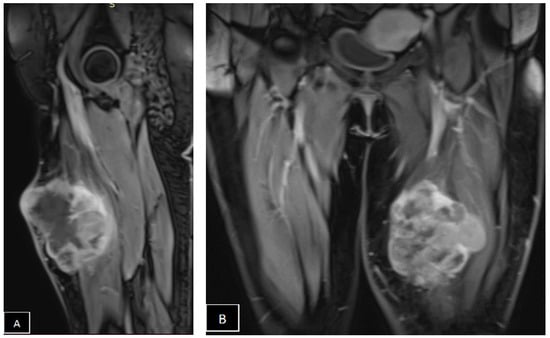

- Spinnato, P.; Clinca, R.; Vara, G.; Cesari, M.; Ponti, F.; Facchini, G.; Longhi, A.; Donati, D.M.; Bianchi, G.; Sambri, A. MRI Features as Prognostic Factors in Myxofibrosarcoma: Proposal of MRI Grading System. Acad. Radiol. 2021, 28, 1524–1529. [Google Scholar] [CrossRef] [PubMed]